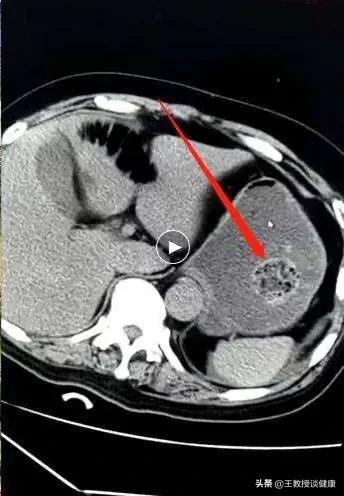

病例二:患者女,81歲,以突發陣發性腹痛加重,伴有噁心嘔吐,不排便不排氣兩天收入我科。腹部CT檢查可以看到患者的小腸高度擴張,呈現急性腸梗阻的徵象,並可看到一個巨大“糞石”。追問病史,患者在入院兩週前一次食用大量冬棗、柿子和海帶絲,食後第二天就感覺腹部不舒服,隱隱作痛,後來腹痛加重而來院治療。經過系統治療腸梗阻無改善,遂行急診手術切開小腸將糞石取出。

CT顯示腸道內巨大糞石